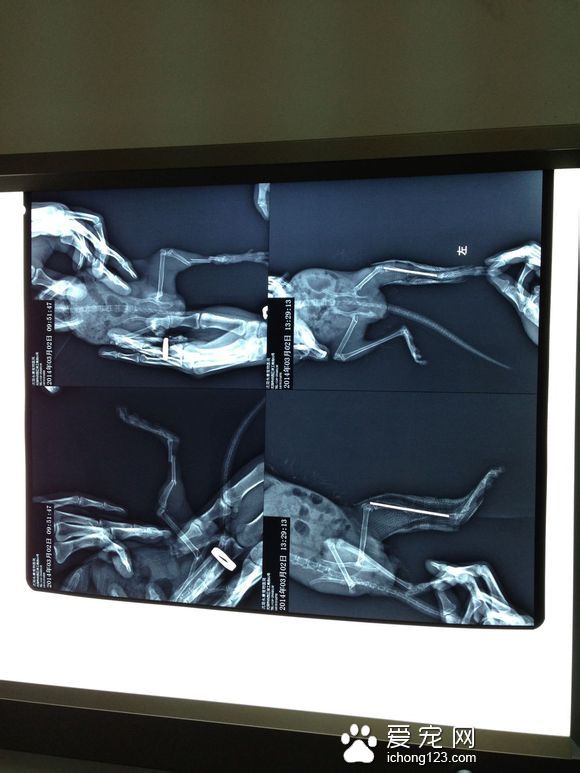

龙猫骨折怎么办? 龙猫发生骨折后,应先去宠物医院拍片看看病情轻重,不要期待它能自己愈合。 龙猫属于啮齿类动物,恢复力非常好,不太严重的骨折,减少活动量,一般都能很快恢复。 龙猫骨折症状: 如果是闭合性骨折,其骨折症状为:皮肤没破、断骨没扎出,可以自己凭感觉把断骨对接好,上夹板固定。 如果是闭合性粉碎性骨折(碎裂3块以上的)或开放性骨折(皮肤破损、断骨戳出),一定要送去宠物医院治疗。

龙猫骨折治疗: 龙猫骨折后要将龙猫放置在较安静的地方避免惊扰,撤去笼内跳板。 对于骨裂和轻微错位可自己采取外固定。 如果龙猫骨折较严重应去医院做固定,固定方式一般有内固定和外固定两种。 一般采取外固定方式,但因为小动物耐受性很差,往往固定不住。 如果骨折很严重可进行内固定和缝合,但注意麻药的剂量,麻醉的死亡率也是非常高的。 |